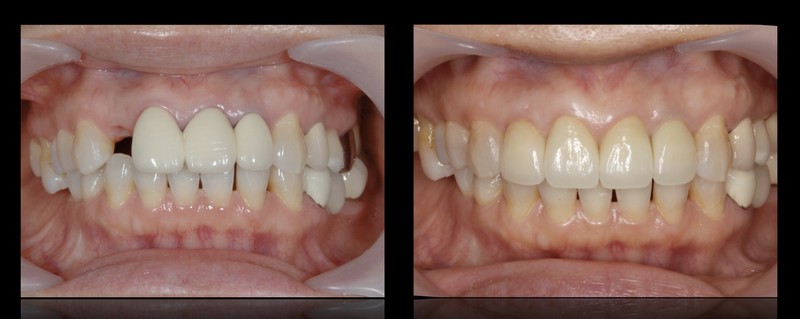

前牙美學植牙